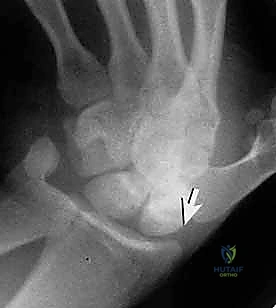

- الأشعة السينية الخاصة (Scaphoid Views): الأشعة السينية العادية للرسغ قد لا تظهر الكسر. يطلب الدكتور هطيف وضعيات تصوير محددة (أربع وضعيات مختلفة مع انحراف اليد) لتوضيح عظم الزورقي بشكل كامل. مع ذلك، ما يقارب 15% إلى 20% من كسور الزورقي تكون "خفية" (Occult Fractures) ولا تظهر في الأشعة السينية في الأسبوع الأول.

- الأشعة المقطعية (CT Scan): يفضل الأستاذ الدكتور محمد هطيف استخدام الأشعة المقطعية ثلاثية الأبعاد (3D CT Scan) للتخطيط الجراحي. فهي توفر خريطة دقيقة جداً لحجم الكسر، زاوية الانحراف، وتساعد في تحديد مسار المسمار بدقة مليمترية قبل الدخول إلى غرفة العمليات.